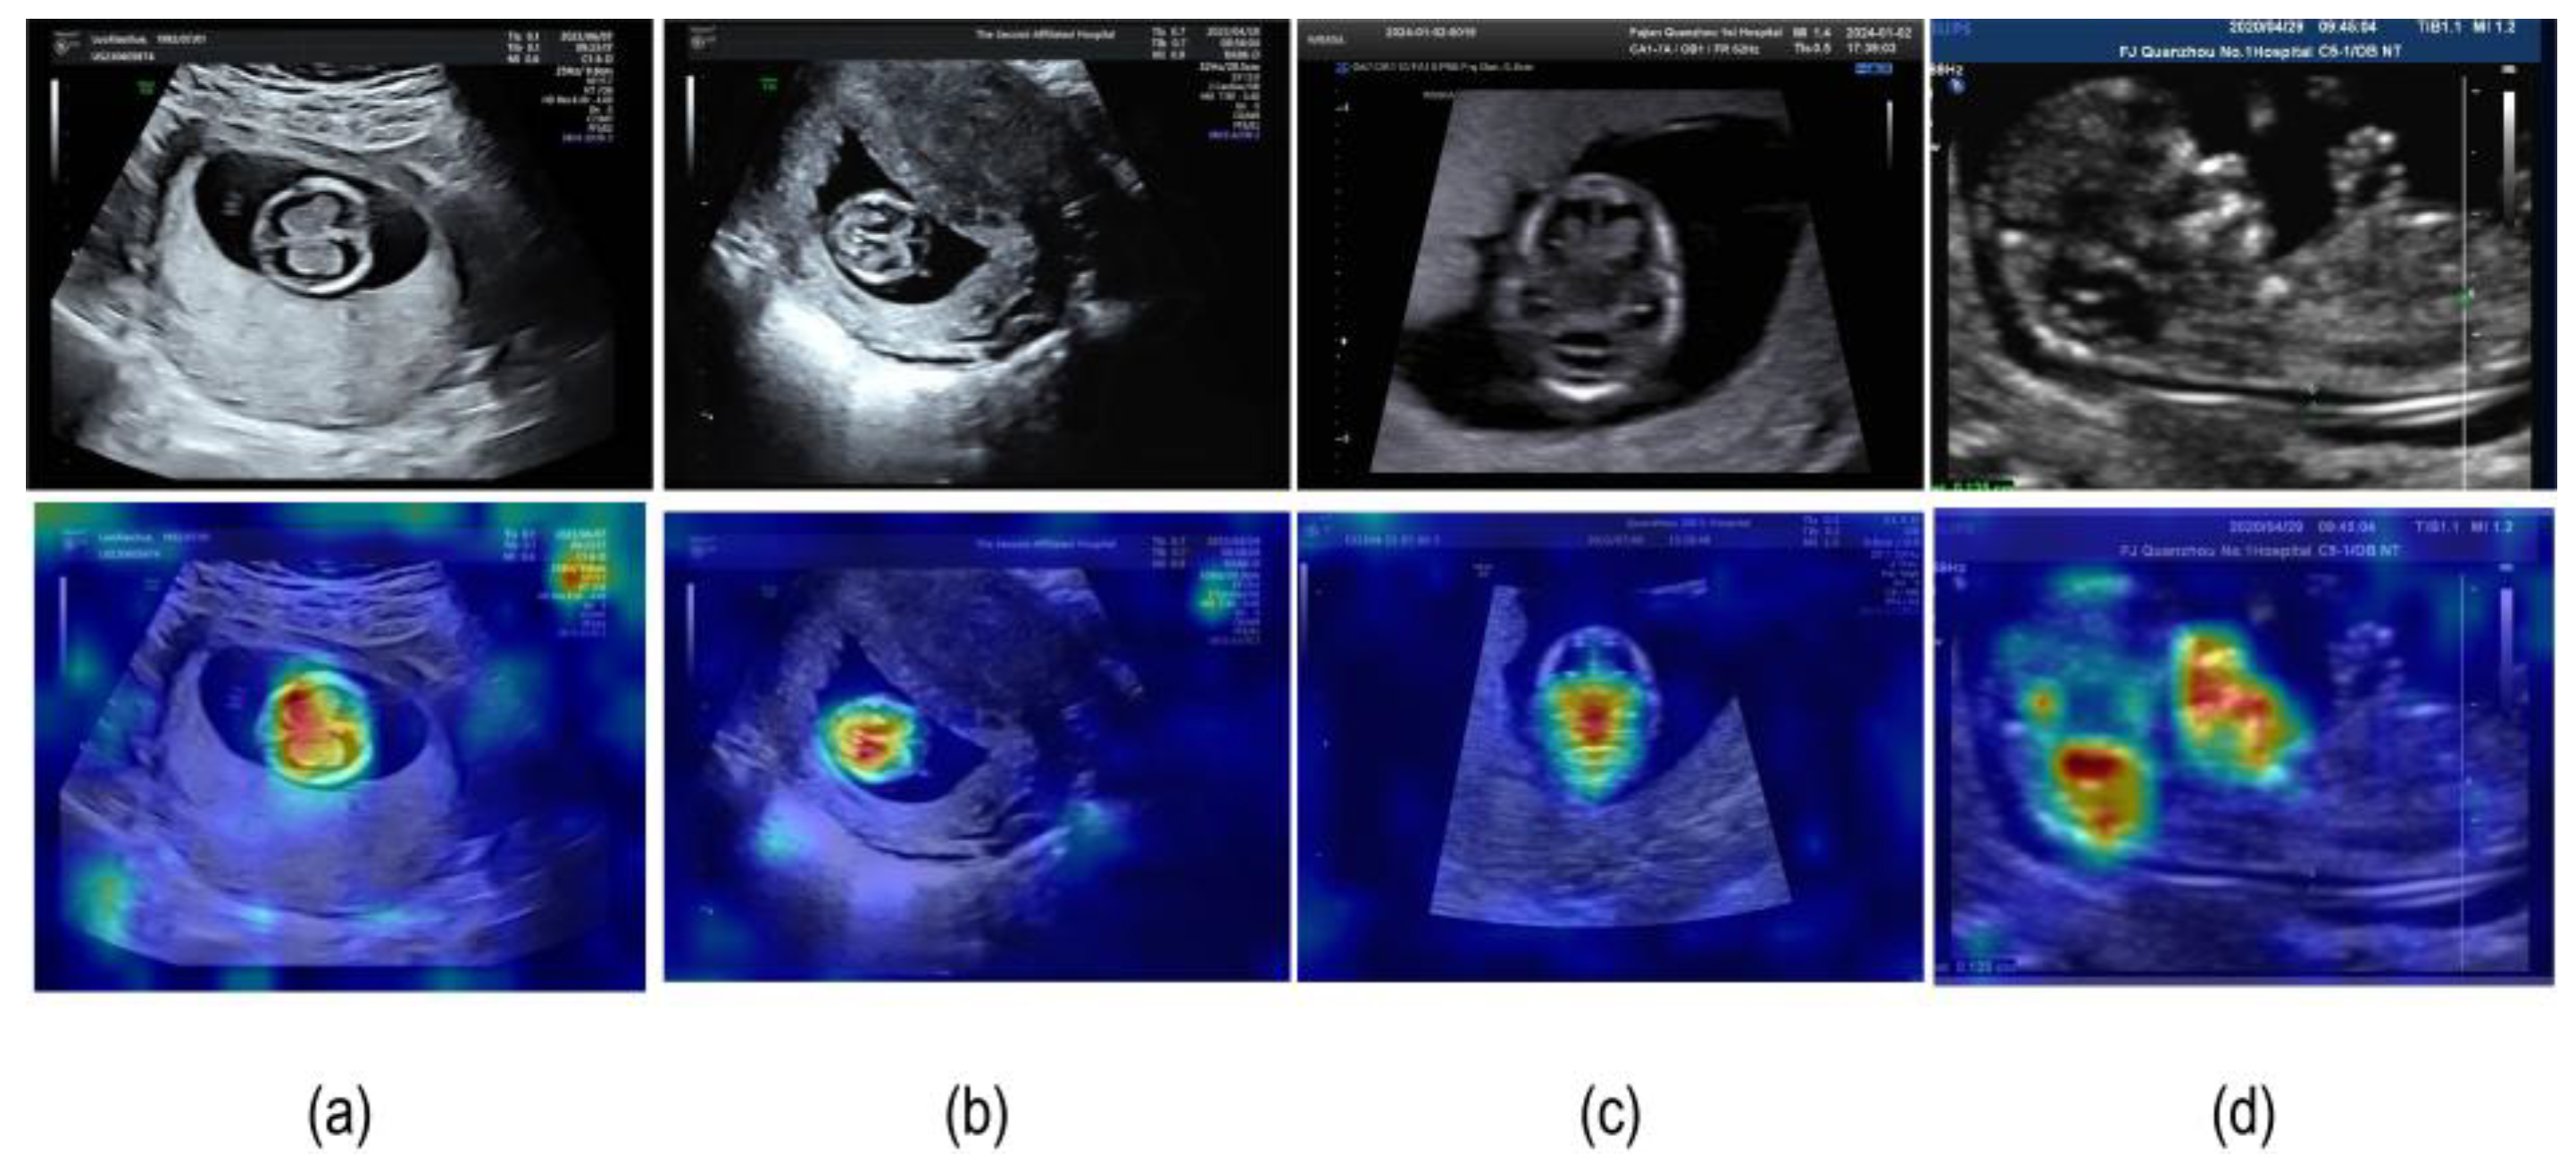

4.3.2. Model Visualization Results